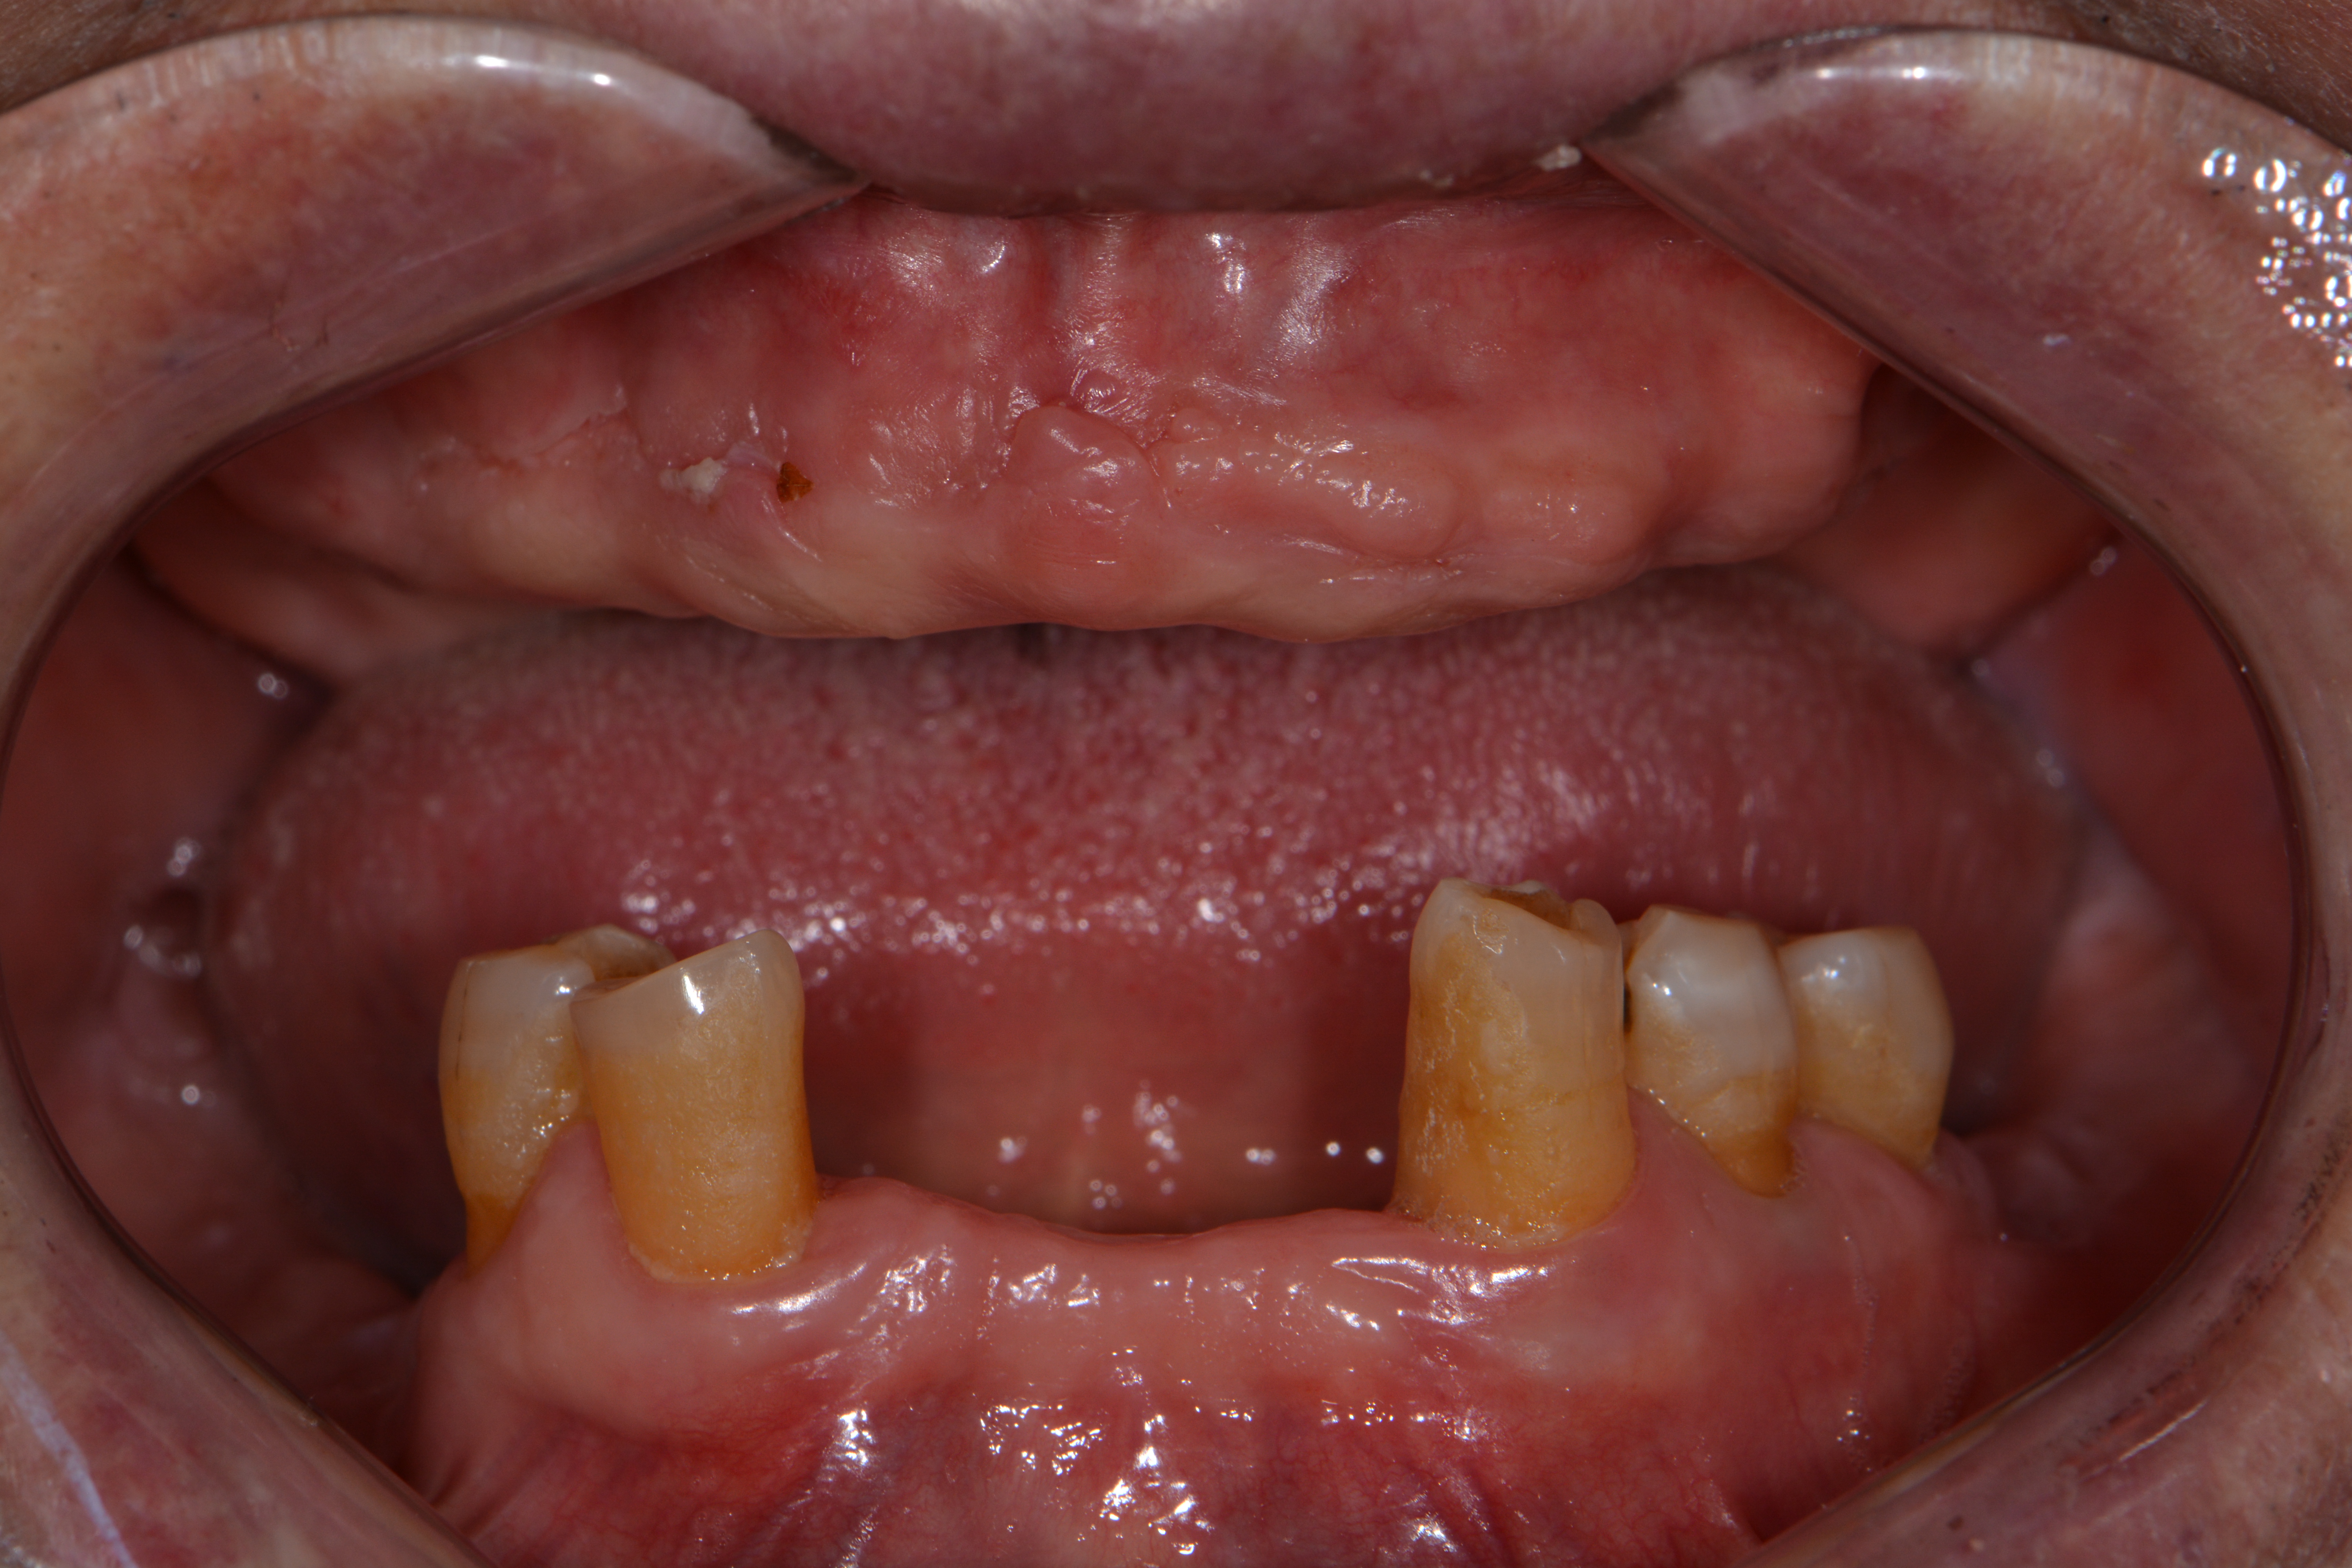

상악 완전틀니, 하악 부분틀니

Before

아래 쪽에 간혹 튼튼한 치아가 몇개 남아있을 때가 있습니다.

이런 치아는 발치하지 않고 부분틀니를 지지해주는 치아로 활용하게 되면

저작 만족도를 높일 수 있습니다.